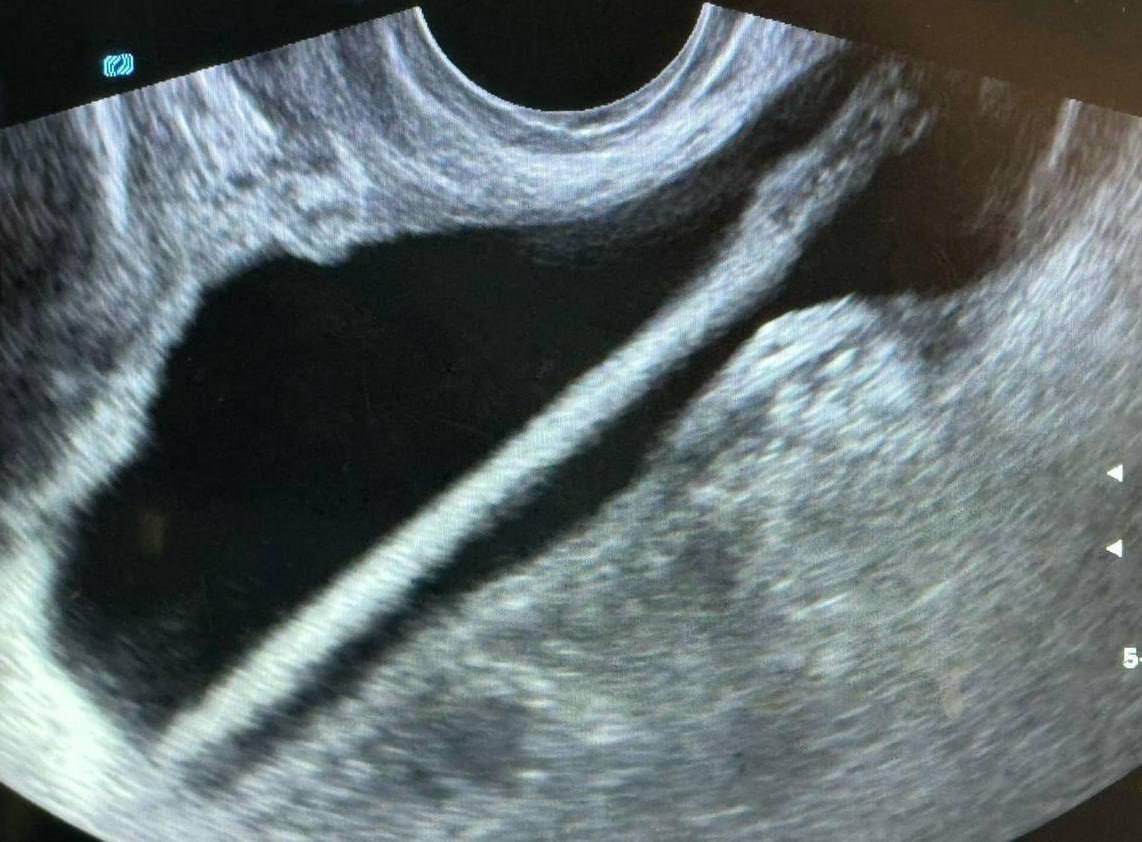

В Подмосковье врачи достали из мочевого пузыря женщины косметический карандаш.

Засунула его туда 46-летняя женщина сама. Специалисты на этом фоне призвали не экспериментировать с собственным организмом.